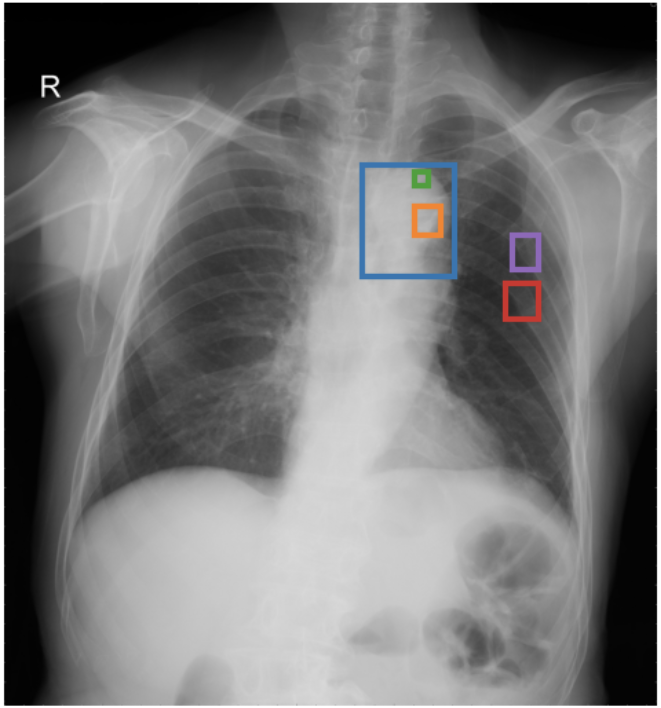

4.3 Qualitative Analysis

Figure 3 shows phrase grounding results for the phrase “Chronic inflammatory changes predominantly in both lung apices” on an image from PadChest-GR [11]. Both CURE and MAIRA-2 successfully identify the lung apices associated with the described findings. However, CURE’s localization is more accurate and better aligned with the phrase semantics, while MAIRA-2 provides a coarser prediction that only partially covers the relevant areas. As expected, MedGemma-4B-IT does not produce visual grounding outputs, and thus no bounding boxes are shown for this model.